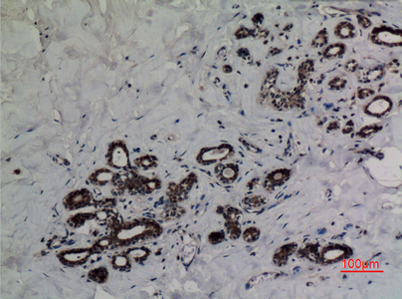

Product name: p53 (Acetyl Lys382) rabbit pAb

Dilutions: Western Blot: 1/500 - 1/2000. IHC-p: 1:100-300 ELISA: 1/20000. Not yet tested in other applications.

Immunogen: Synthesized acetyl-peptide derived from the human p53 around the acetylation site of K382.